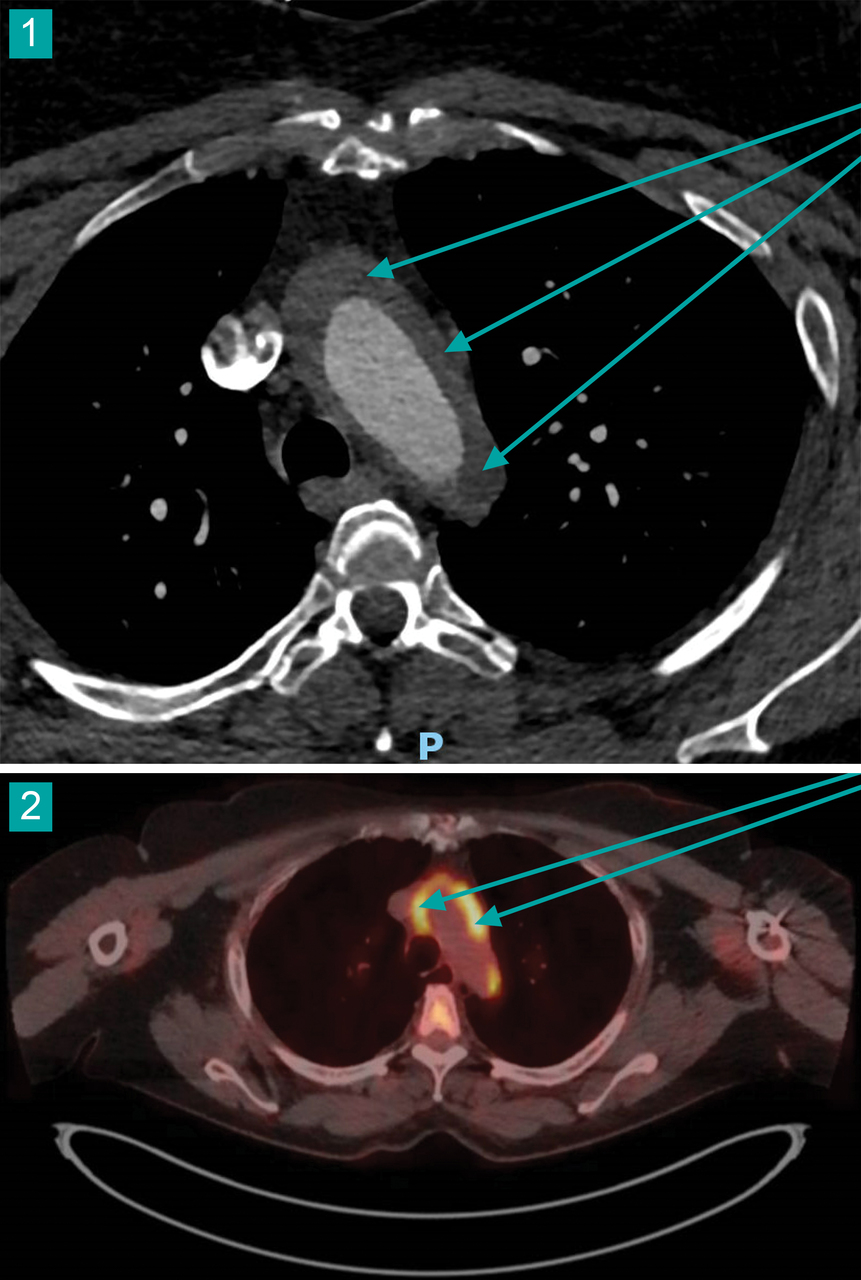

Une femme de 36 ans consulte pour une hypertension artérielle sévère et des douleurs thoraciques. L’électrocardiogramme (ECG) est normal. Un scanner thoracique est réalisé (fig. 1), complété par une tomodensitométrie à émission de positons (TEP-scan) au 18-FDG (fig. 2).

L’angioscanner de l’aorte (fig. 1) retrouve un épaississement pariétal circonférentiel non sténosant de la crosse aortique mesurant 9 mm, de l’aorte abdominale sous-rénale, de la bifurcation aortique et des deux artères iliaques communes ainsi qu’une sténose de l’artère rénale gauche, avec un rein droit hypotrophique.

Le TEP-scan au 18-FDG (fig. 2) montre un hypermétabolisme circonférentiel aortique franc de la crosse aortique et d’une partie de l’aorte thoracique ascendante sur environ 7 cm (SUV [standardized uptake value ou, en français, valeur de fixation normalisée] max : 6,3), ainsi que de l’aorte sous-rénale et de la partie initiale des deux artères iliaques primitives, sur environ 6 cm (SUV max : 7,9).